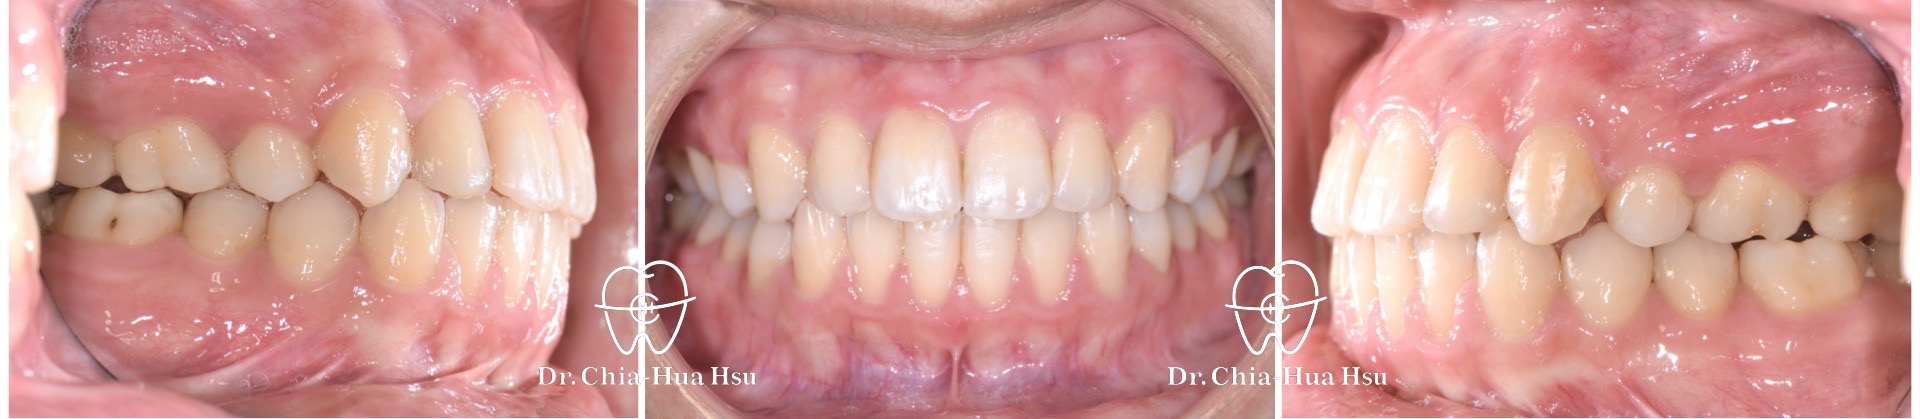

- 病患主訴:前牙錯咬、再次矯正治療。

- 問題分析:患者有前牙錯咬(反咬)、後牙錯咬的問題。

- 治療方式:使用傳統金屬矯正器,使用原有骨釘將上顎牙齒前移,迅速將療程結束。

- 治療時間:1 年 3 個月。

- 治療結果:齒列排齊,笑容更燦爛。

治療前

治療後